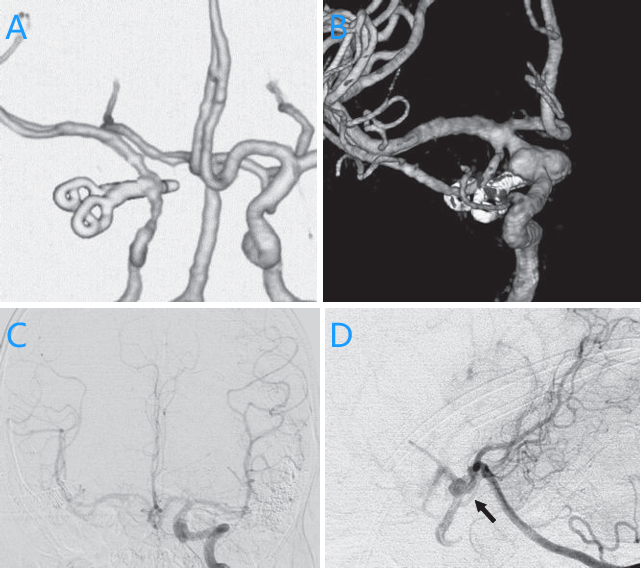

第二次手术前的血管造影揭示了一个令人忧心的景象:整个ICA从右侧前壁向内侧壁扩张,右侧大脑中动脉(MCA)清晰,PCOM从动脉瘤近端的ICA分化延伸(图C&D),手术难度升级。

- A,第一次手术后进行的三维计算机断层扫描,显示没有残余动脉瘤。

- B,第二次手术前前斜侧切面数字减影血管造影,显示夹子附近的颈内动脉前内侧部分动脉瘤复发。

- C, 左侧颈内动脉前正位血管造影,并进行 Matas 试验,显示第二次手术前通过前交通动脉向右侧大部分中谷动脉区域提供了良好的侧支血流。

- D,左侧椎动脉侧位血管造影和 Alcock 试验,显示第二次手术前通过后交通动脉的侧支血流良好。箭头:后交通动脉。